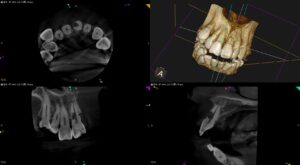

歯に穴が空いてしまった。。。前歯なので抜きたくない。なんとか残せないだろうか?〜#9 Invasive cervical root resorption repair, RCT 1回法

紹介患者さんの治療。 主訴は、 前歯に穴が空いていると言われ抜歯する必要があると言われたた…なんとか残せないだろうか? である。 Pre-op Endo Test(2026.1.28) #9の頬側に大きな穴がある。が、根 … 続きを読む 歯に穴が空いてしまった。。。前歯なので抜きたくない。なんとか残せないだろうか?〜#9 Invasive cervical root resorption repair, RCT 1回法